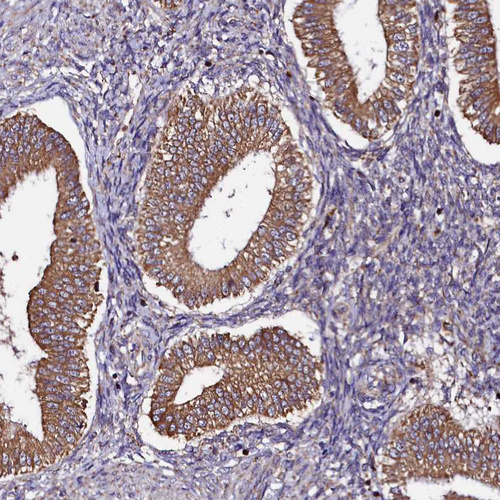

Immunohistochemical staining of human endometrium shows strong cytoplasmic positivity in glandular cells.